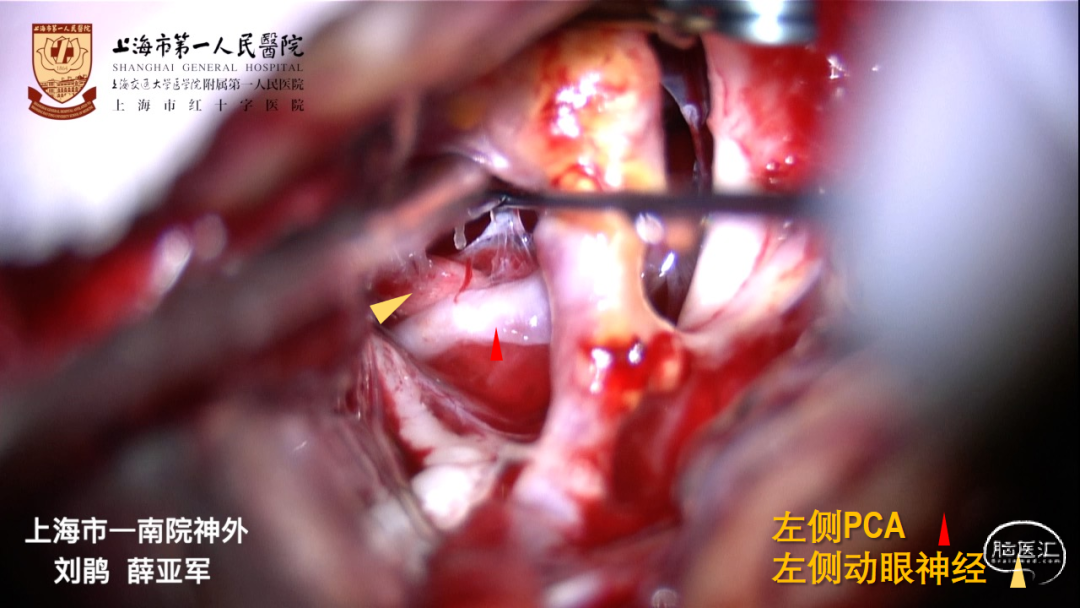

CTA:左侧大型后交通动脉瘤,指向后、外、下

大型动脉瘤,形态复杂:发自ICA后外壁,宽颈、后交通动脉自瘤颈发出

胚胎型后交通动脉,必须保留

GCS13-14分,左侧动眼神经麻痹,右侧肢体肌力IV-

动脉瘤形态复杂